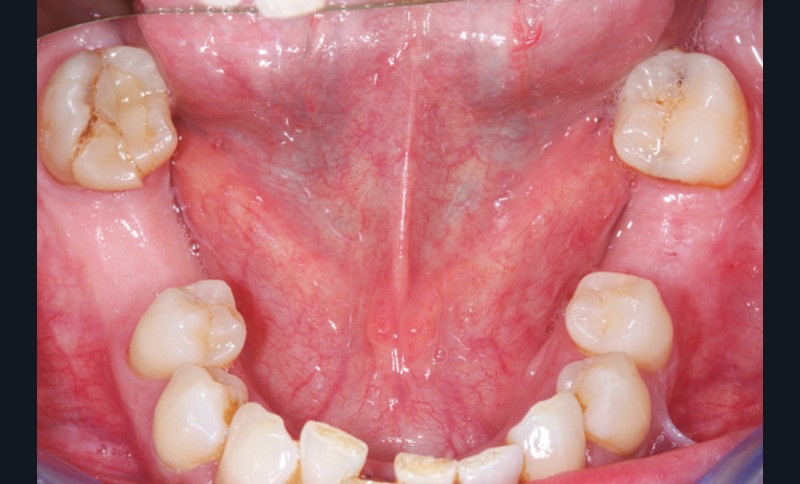

La perte d’une ou plusieurs dents entraîne la perte des points de contact, responsables de la stabilité et de la continuité de l’arcade. Par conséquent, une avulsion a pour première conséquence la migration ou la version d’une ou plusieurs dents distales (fig. 1 et 2). Cela est vrai en antérieur comme en postérieur.

L’âge de survenue de l’extraction semble avoir une importance sur l’apparition des migrations et des versions : si l’édentement intervient après 26 ans, les conséquences sont moins fréquentes [9].